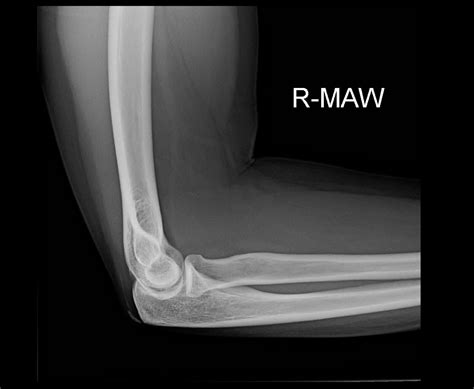

• Imaging tests: X-rays, ultrasound, or MRI scans can help visualize the calcium deposits and assess the extent of the damage.